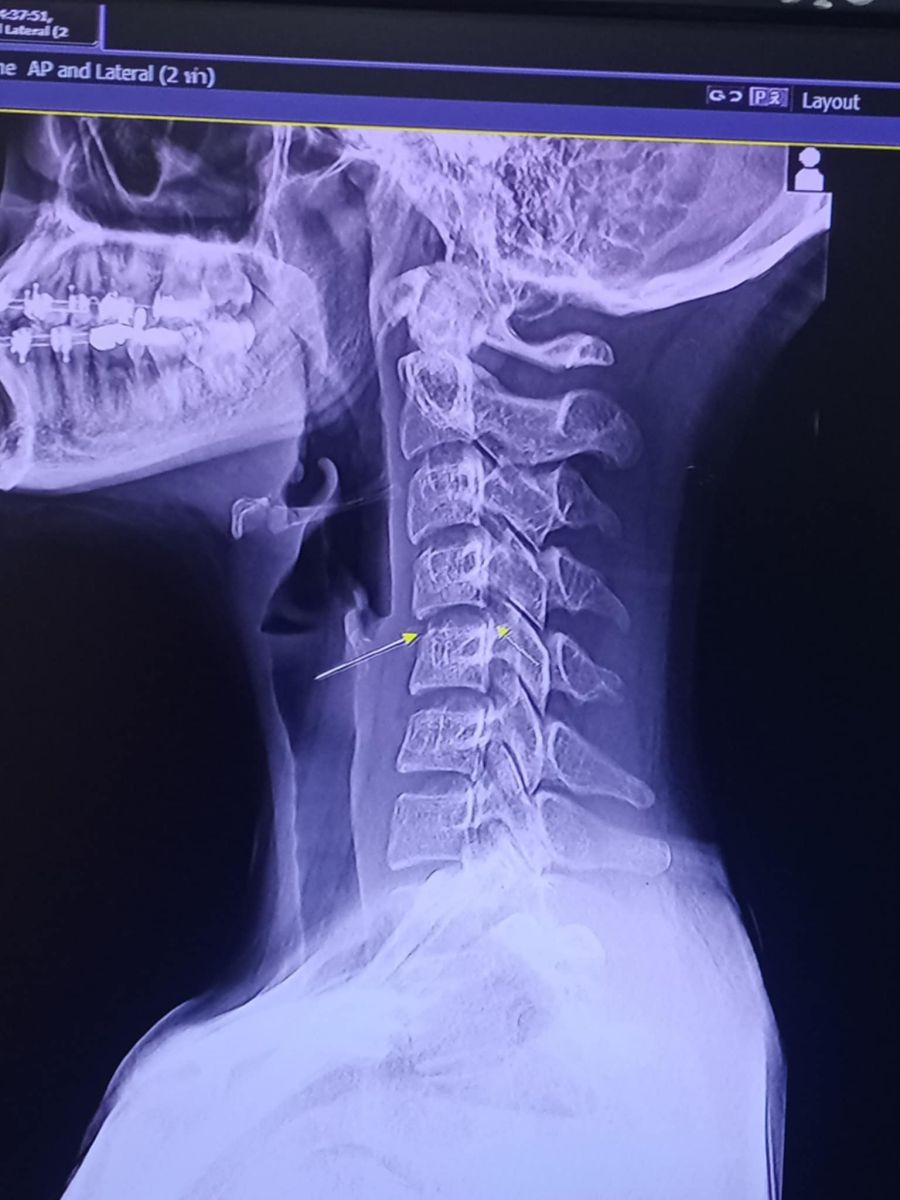

ผู้สื่อข่าวรายงานว่า จากกรณี น้องผิง น.ส.ชญาดา อายุ 20 ปี นักร้องสาวรถแห่ ชาวบ้านแดง ต.บ้านแดง อ.พิบูลย์รักษ์ จ.อุดรธานี เสียชีวิตจากไปนวดคลายเส้นกับหมอนวดที่หนองประจักษ์ เขตเทศบาลนครอุดร คาดว่าจะถูกหมอนวดผิดในท่าบิดคอ จนทำให้กระดูกคอเคลื่อนไปทับเส้นประสาท สุดท้ายเป็นเจ้าหญิงนิทรากว่า 2 เดือน โดยญาติๆ ได้นำร่างของน้องผิง กลับไปบำเพ็ญกุลที่บ้านเกิด ยังไม่มีกำหนดฌาปนกิจศพ

ล่าสุด วันนี้ 9 ธันวาคม 2567 เวลา 09.00 น. สำนักงานสาธารณสุข จ.อุดรธานี ดร.นพ.สมชายโชติ ปิยวัชร์เวลา นายแพทย์สาธารณสุข จ.อุดรธานี ตั้งโต๊ะแถลงข่าวชี้แจงว่า ผลชันสูตรจากแพทย์พบว่า น.ส.ชญาดา เสียชีวิตจากการติดเชื้อในกระแสเลือด และมีเชื้อราร่วมด้วย ทางแพทย์ไม่ยืนยันว่าเกิดจากการนวด ซึ่งหากญาติติดใจ สามารถร้องขอตำรวจชันสูตรพลิกศพได้ ไม่เกี่ยวกับสาธารณสุข เป็นเรื่องของตำรวจแล้ว ส่วนประเด็นร้านนวด ทางเจ้าหน้าที่ฯ ได้ลงพื้นที่พบว่าจดแจ้งใบอนุญาตสถานประกอบการถูกต้อง ส่วนหมอนวดทั้งหมด มีใบประกาศสำหรับนวด ทางร้านจึงไม่มีความผิดใดๆ สามารถเปิดต่อไปได้ แต่ทราบว่าเจ้าของร้านได้ปิดให้บริการชั่วคราว